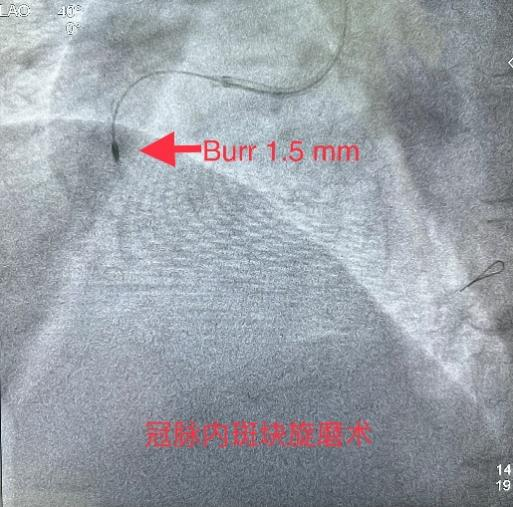

3月8日经过充分的术前准备,雷新军教授带领景林德博士和蔡安琪医生按照预定方案为患者实施了手术。冠脉造影示:RCA 2段慢性闭塞合并重度钙化,闭塞段长约30 mm,同向桥侧支供血使其远段显影(图3a);前降支散在斑块伴钙化,狭窄约25%-50%,并通过间隔支侧支循环向右冠逆向供血(图3b);回旋支11段狭窄约75%(图3c)。决定干预右冠:指引导管到位后在Guidezilla的支撑下,经Corsair微导管仔细操控GAIA 3rd穿过闭塞段进入远端血管真腔(图3d,e);然后通过微导管交换成旋磨导丝,使用1.5 mm Burr进行冠脉内斑块旋磨并抛光(图3f),造影见右冠恢复TIMI 3级前向血流,但2段残余狭窄最重处仍达90%(图3g);遂经导丝送入3.0*12 mm“Shockwave”冲击波球囊分段进行血管内碎石术:首先将压力充盈至4 atm后开始释放脉冲,松解钙化斑块,然后再将充盈压升至6 atm维持10秒,对靶病变进行低压球囊扩张成形(图3h);再次造影见右冠2段局限性夹层,闭塞段残余狭窄<10%(图3i),效果非常满意,遂由远及近衔接植入BioFreedom支架(图3j),历时约1小时手术成功,病人安返病房。

图3 经皮冠脉介入治疗